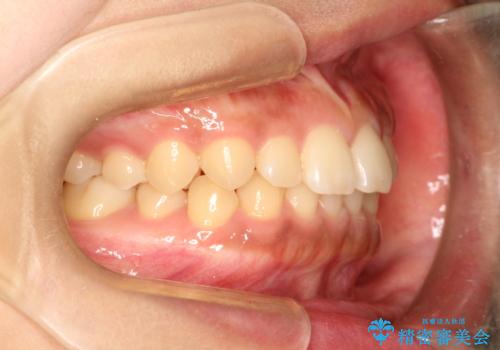

前歯の隙間を閉じたい。インビザラインによる治療

- 前歯の隙間を閉じたいと矯正カウンセリングに来られた患者様です。

マウスピース矯正(インビザライン)を行い短期間で治療が完了しました。